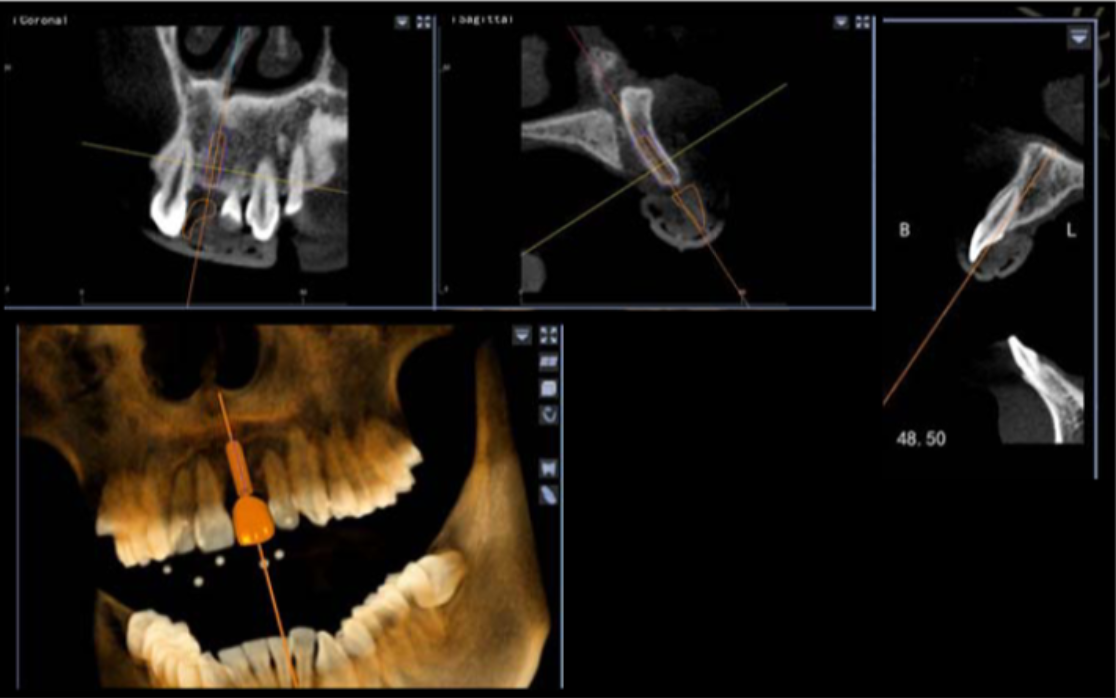

此病例中主刀醫(yī)生借助迪凱爾數(shù)字化口腔種植手術(shù)導(dǎo)航系統(tǒng),精確的控制每鉆的定點(diǎn)精度和角度,保證了每次制備定點(diǎn)誤差小于0.4mm,角度偏差不大于3.5°,極大的保證了種植體按照種植前的手術(shù)設(shè)計(jì)就位。

避免骨劈開及切牙管,這是由華西口腔的楊醒眉教授主刀的一次完美的前牙美學(xué)區(qū)數(shù)字化種植手術(shù)的病例!